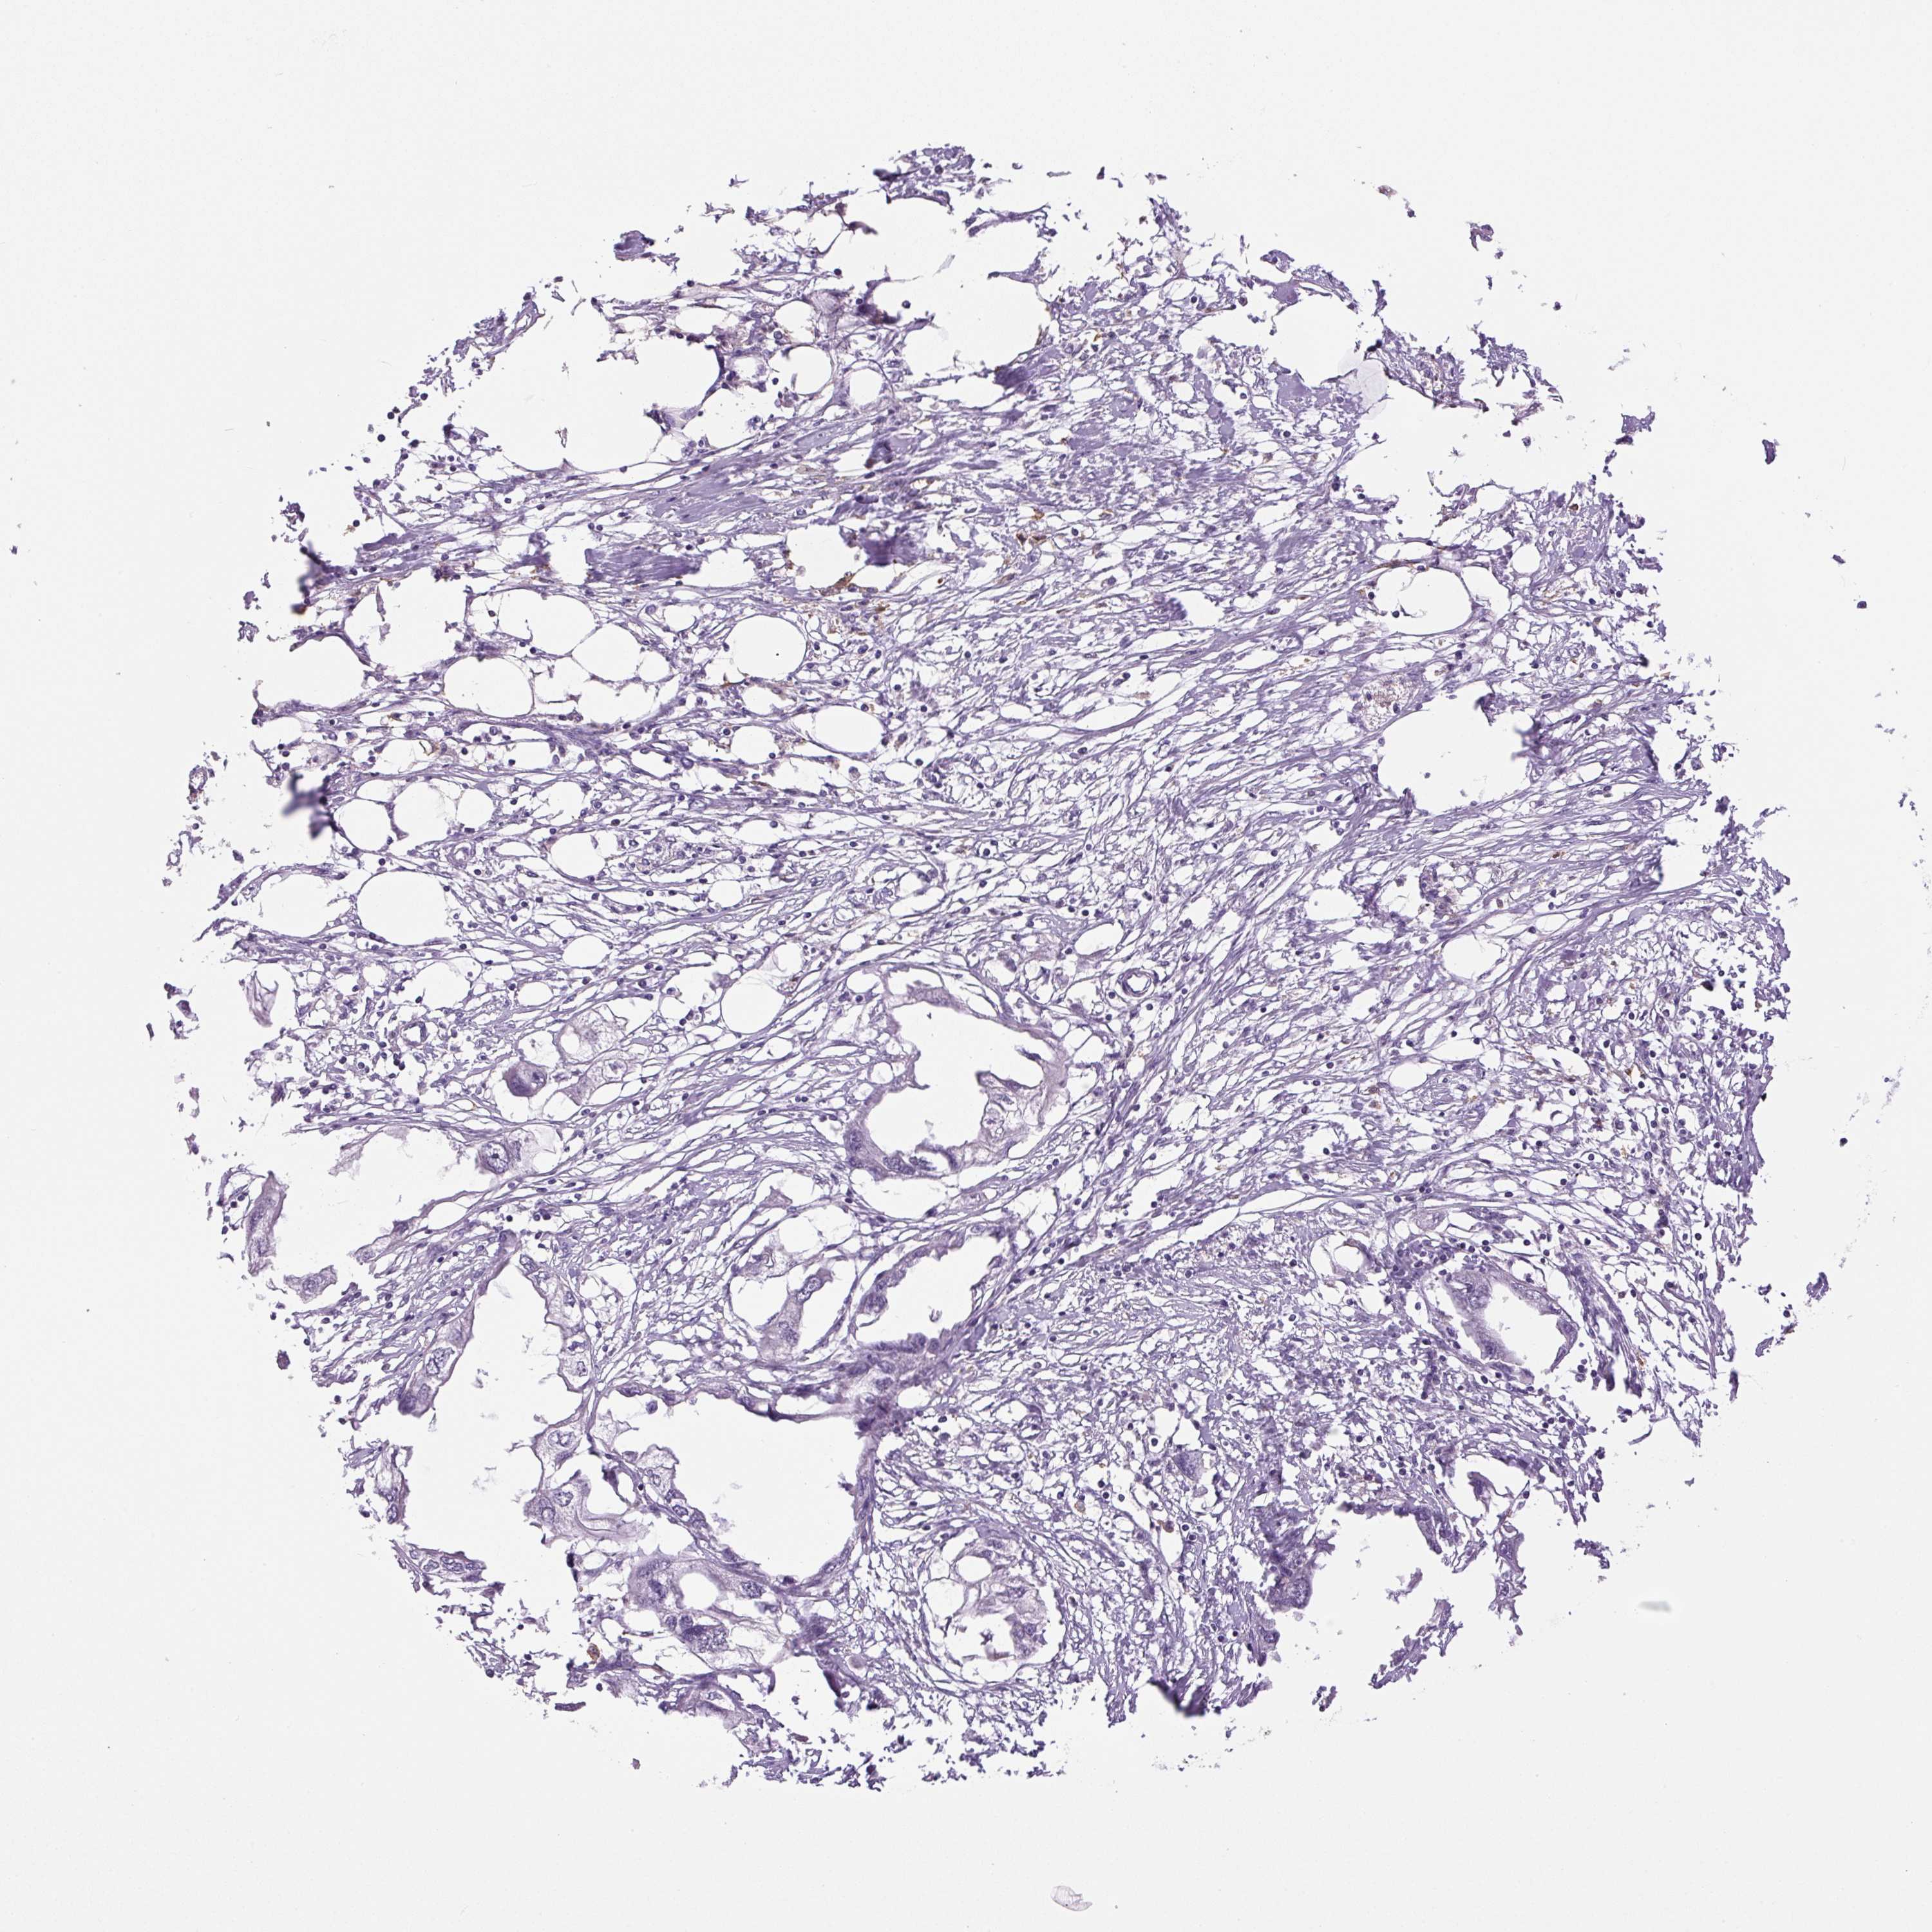

ENDOMETRIAL CANCER - Protein expressioni

A mouse-over function shows sample information and annotation data. Click on an image to view it in a full screen mode. Samples can be filtered based on level of antibody staining by selecting one or several of the following categories: high, medium, low and not detected. The assay and annotation is described here.

Note that samples used for immunohistochemistry by the Human Protein Atlas do not correspond to samples in the TCGA dataset.

Antibody stainingi

Antibody staining in the annotated cell types in the current human tissue is reported as not detected, low, medium, or high, based on conventional immunohistochemistry profiling in selected tissues. This score is based on the combination of the staining intensity and fraction of stained cells.

Each image is clickable and will lead to virtual microscopy that enables deeper exploration of all samples and also displays staining intensity scores, fraction scores and subcellular localization as well as patient and tissue information for each sample.

Antibody HPA052590

Antibody HPA053608

Staining

High

Medium

Low

Not detected

Intensity

Strong

Moderate

Weak

Negative

Quantity

>75%

75%-25%

<25%

None

Location

Nuclear

Cytoplasmic/membranous

Cytoplasmic/membranous,nuclear

Adenocarcinoma, NOS